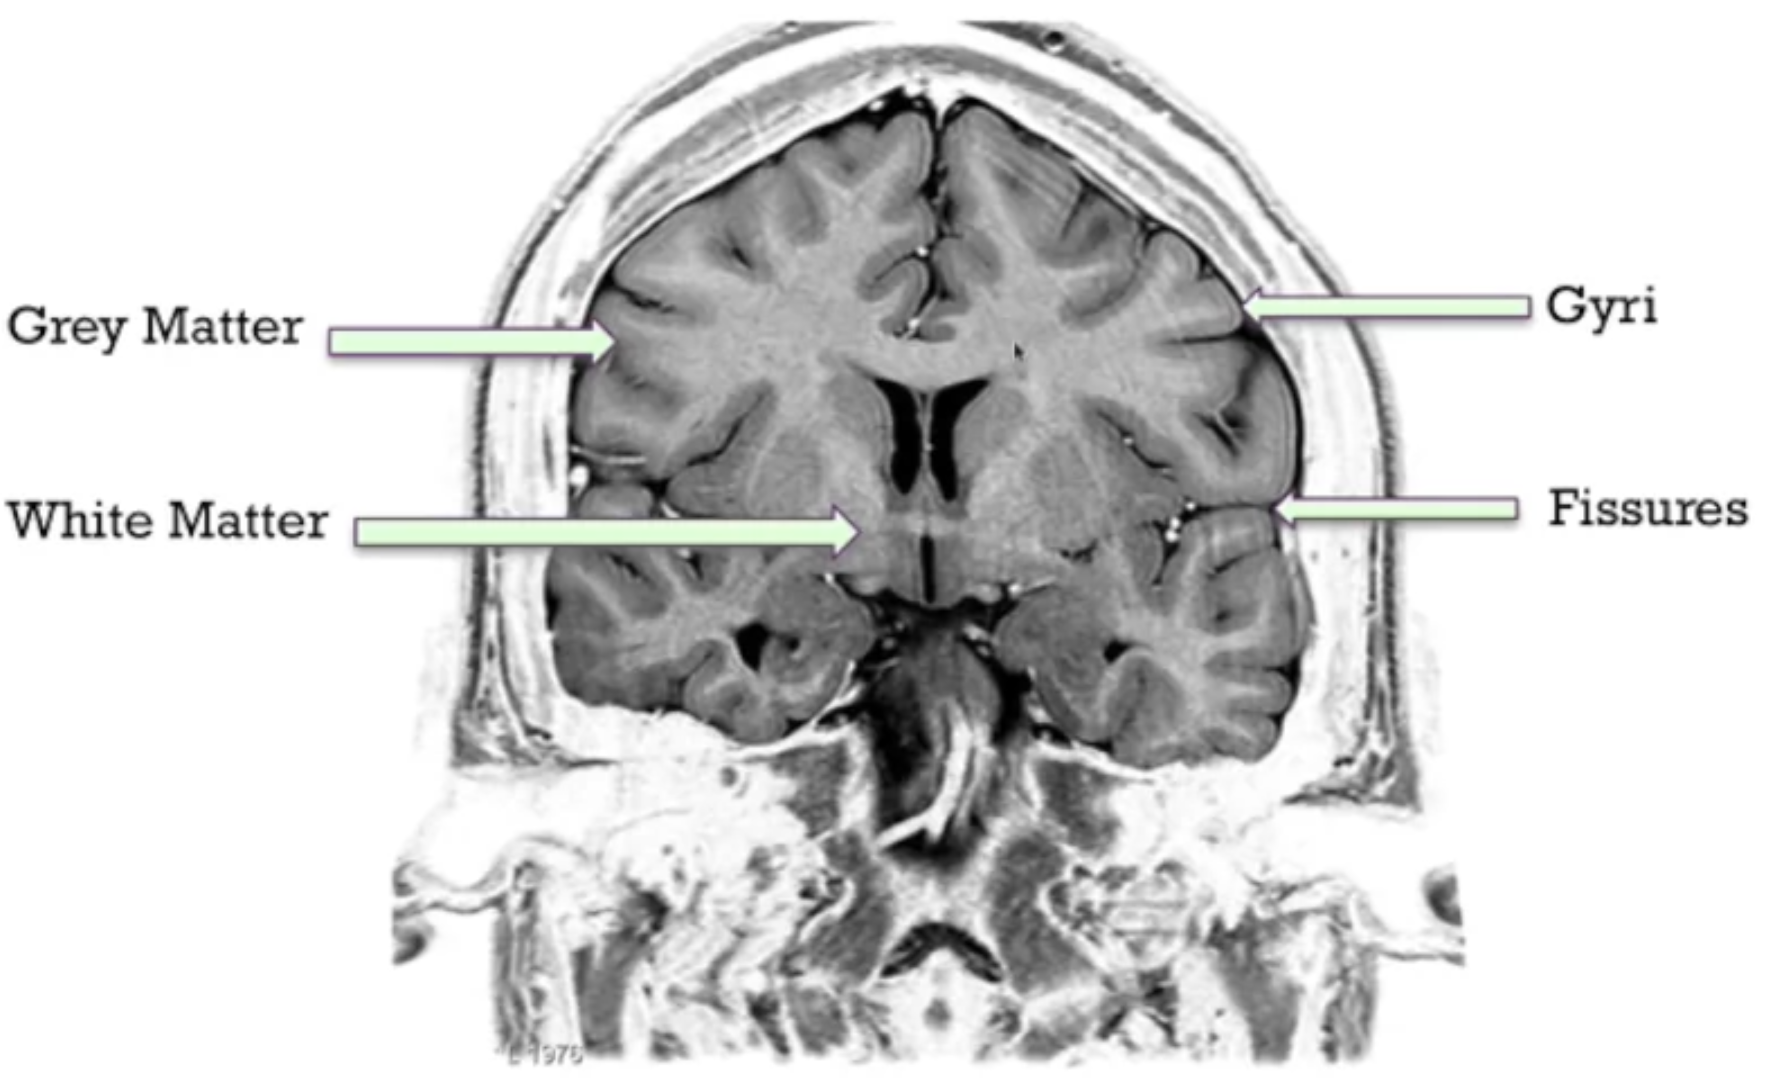

- White matter

- Gives structure

- Delivers nutrients

- Provides communication

- Grey matter

- Computations happen here

- The fissures exist to fit as much as grey matter into the skull (increase surface area)